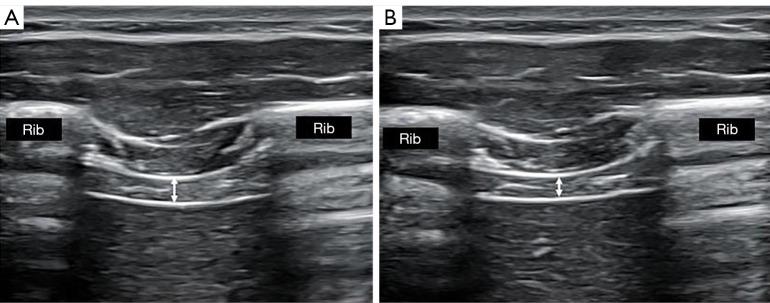

The diaphragm is considered the main muscle involved in breathing and also linked to trunk stabilization functions. Up to date, rehabilitative ultrasound imaging (RUSI) has been the most used technique to evaluate unilaterally the transcostal diaphragm thickness. Nevertheless, the inspiratory activity of both hemi-diaphragms is bilaterally performed at the same time, and its simultaneous evaluation with a thoracic orthosis could improve its assessment as well as its re-education with visual biofeedback of both hemi-diaphragms at the same time. The purpose was to evaluate the reliability and repeatability of simultaneous thickness measurements of both hemi-diaphragms bilaterally during normal breathing using a thoracic orthosis that allowed bilateral fixation of both right and left ultrasound probes.

METHODS

The study was conducted in 46 healthy subjects, whose diaphragm thickness was measured bilaterally and simultaneously in the anterior axillary line during relaxed breathing with a designed thoracic orthosis and 2 ultrasound tools. Intra-examiner (same examiner), inter-examiner (2 examiners), intra-session (1 hour) and inter-session (1 week) reliability and repeatability between each pair of measurements of diaphragm muscle thickness were analyzed during normal breathing.

膈肌被认为是参与呼吸的主要肌肉,也与躯干稳定功能相关。迄今为止,康复超声成像(RUSI)一直是最常用的单侧评估肋膈角处膈肌厚度的技术。然而,两侧半膈肌的吸气活动是同时双侧进行的,使用胸段矫形器对其进行同步评估,可能会改善对其的评估,以及同时对两侧半膈肌进行视觉生物反馈再训练。目的是评估在正常呼吸过程中,使用一种允许双侧固定左右超声探头的胸段矫形器,双侧同时测量两侧半膈肌厚度的可靠性和可重复性。

方法

该研究在46名健康受试者中进行,使用一种设计的胸段矫形器和2个超声工具,在安静呼吸时于双侧腋前线同时测量膈肌厚度。分析了正常呼吸过程中,每对膈肌厚度测量值之间的检查者内(同一名检查者)、检查者间(2名检查者)、测量时段内(1小时)和测量时段间(1周)的可靠性和可重复性。